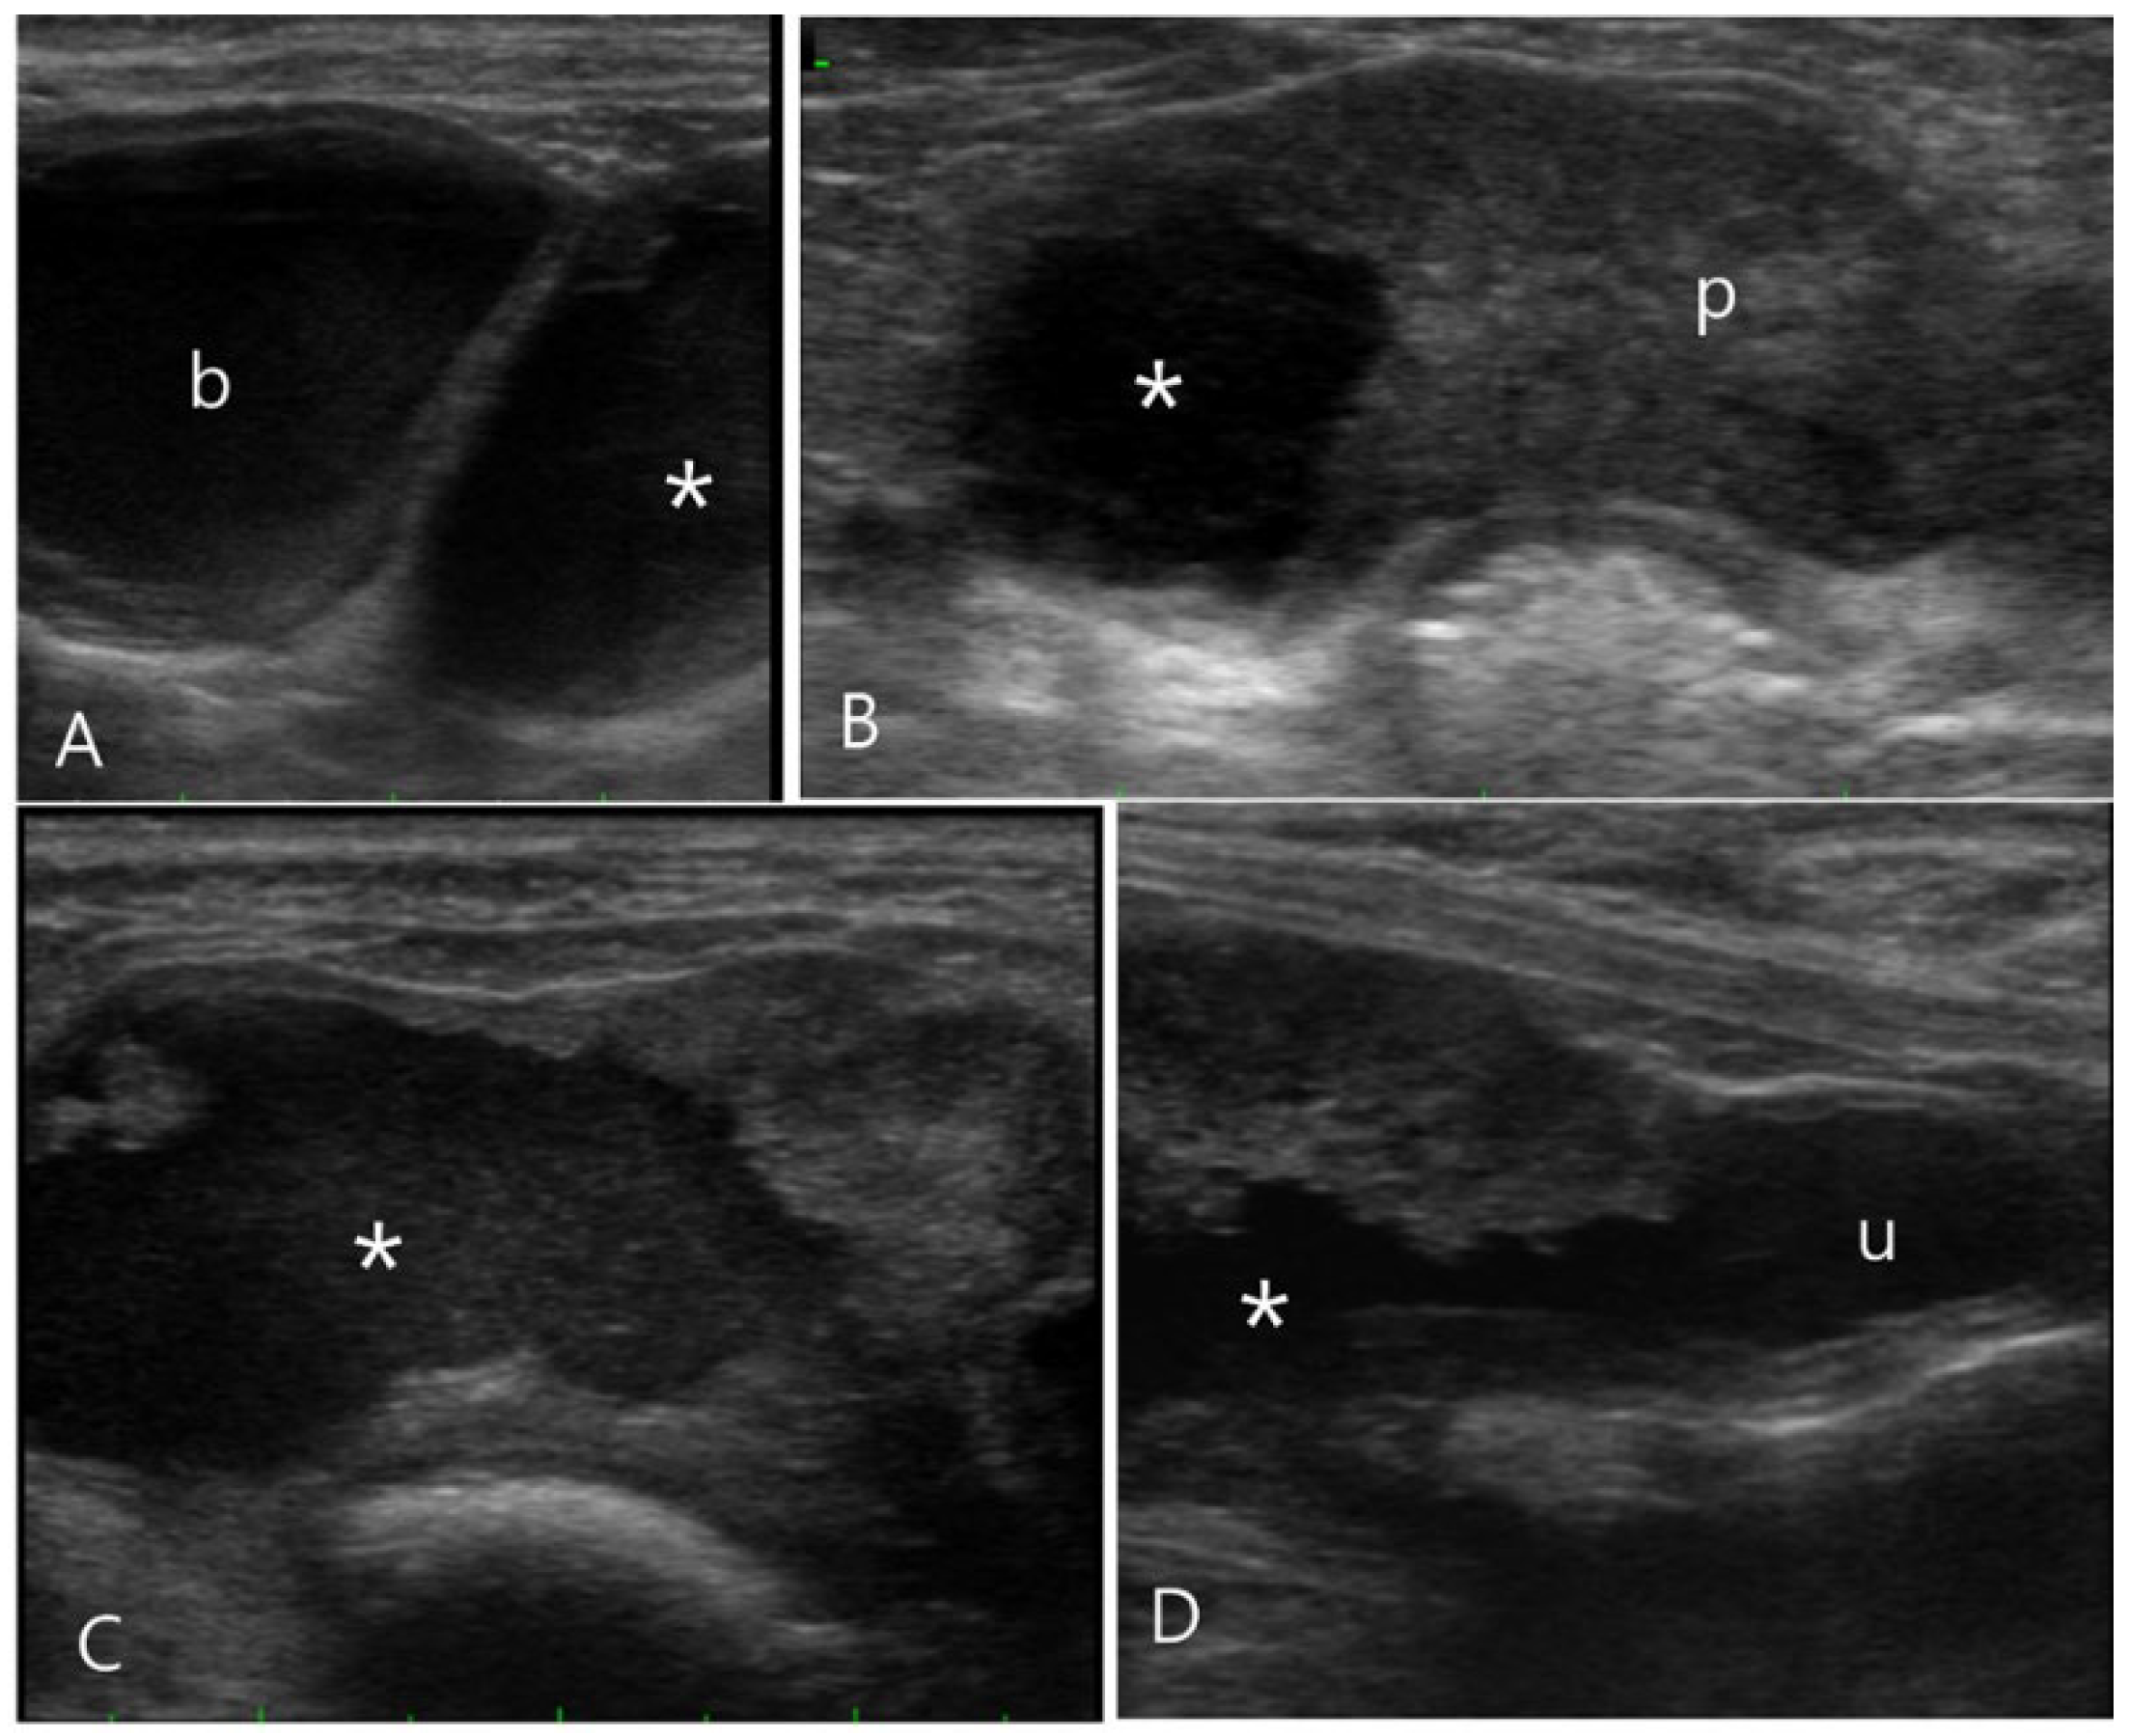

2.3. Case 3